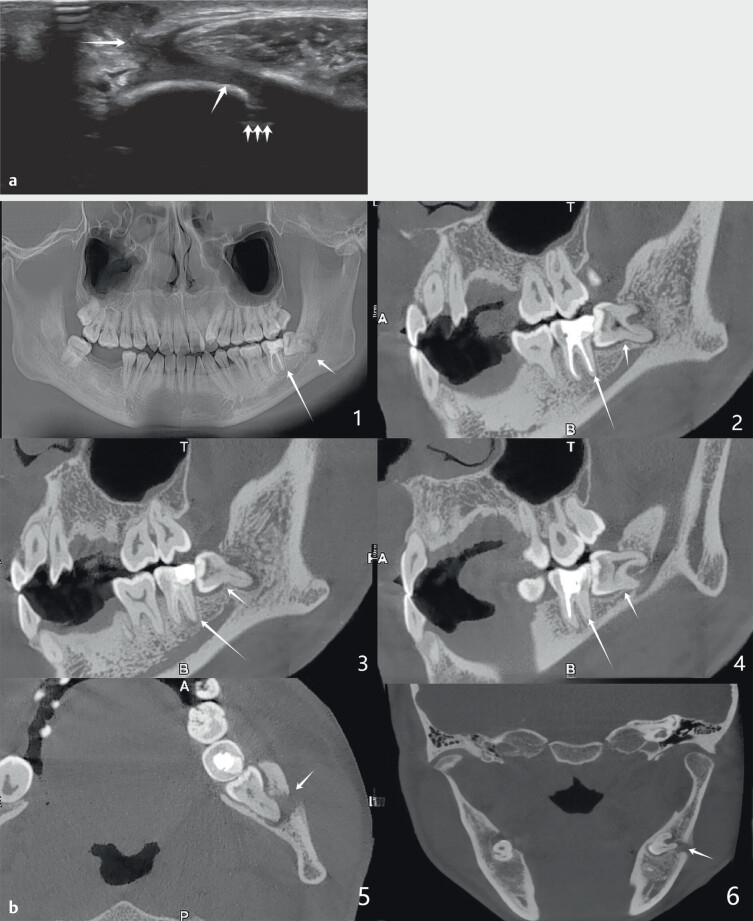

Ultrasonographic Diagnosis of Odontogenic Cutaneous Fistula: A Case Report Demonstrating the Value of Multimodal Imaging Diagnostics.

超声诊断牙源性皮瘘一例:多模态影像诊断价值的证明。